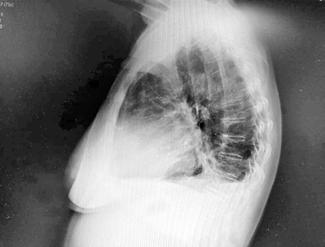

Se revisaron las pruebas solicitadas en Urgencias. En la analítica se en contró una hemoglobina (Hb) de 14 g/dl, un volumen corpuscular medio (VCM) elevado (106μ³) compatible con su historia de alcoholismo o con un déficit de ácido fólico o vitamina B12, una discreta elevación de la proteina C reactiva (13,2 mg/dl) sin elevación de otros reactantes de fase aguda y unas enzimas hepáticas dentro de la normalidad, con la aspartato transfe rasa ligeramente elevada 39 U/L (rango de normalidad: 5-34). Los tóxicos en orina fueron negativos, así como la etanolemia. La radiografía (rx) de tórax mostraba una condensación en el lóbulo superior izquierdo en posi ble relación con la infección tuberculosa diagnosticada en 2011 (Figura 1). La TC -a pesar de no mostrar signos de patología aguda intracraneal, ni masas ni signos de sangrado- sí que mostraba atrofia cerebral con surcos muy marcados, hallazgo no concordante con la edad de nuestro paciente (Imagen 2).

Figura 1. Radiografía de tórax en bipedestación AP y Lat.

Lesiones residuales/cicatriciales en campo superior izquierda, con aumento de densidad de parénquima, bronquictasias y pérdida de volumen, en relación con antecedente de TBC. Parénquima pulmonar derecho aceptablemente ventilado. Siluesta cardiovascular normal.